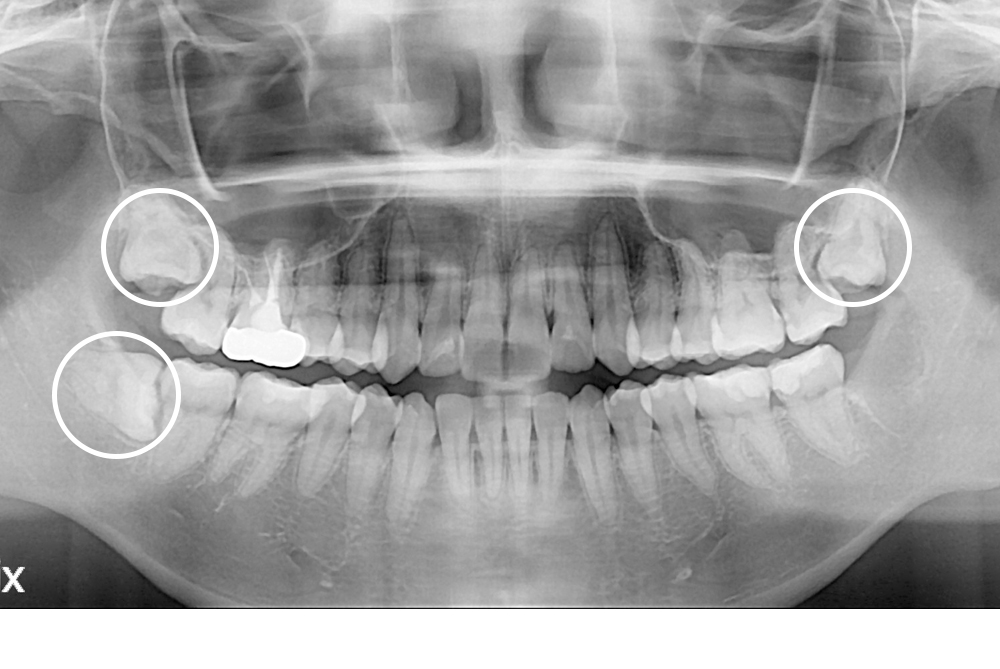

[사랑니] 매복 사랑니 발치

치료후 : 2019-03-09

세종치과는 구강악안면외과학 박사이신 원장님이 발치하는 치과입니다.